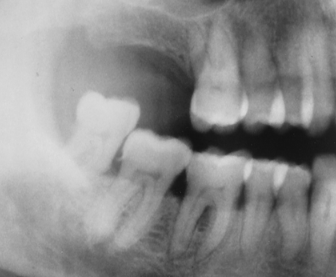

This patient is a 72-year-old man. Notice that the pulp and root canal spaces are significantly diminished. What is the cause of this?

attrition and age

Note the dilacerated premolar root. The condition that affects this sinus is

acute sinusitis

chronic sinusitis

sinus elongation

pneumatization